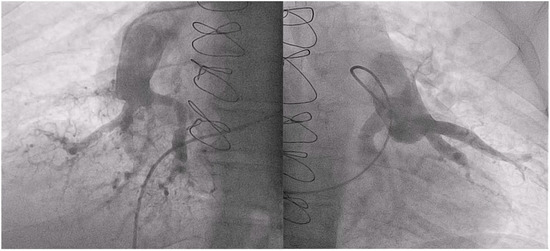

2.2. Balloon Pulmonary Angioplasty Procedure

- Velázquez, M.; Maneiro, N.; Lareo, A.; Albarrán, A.; Huertas, S.; Olazábal, A.; Delgado, J.; Alonso, S.; Sarnago, F.; Tejada, J.G.; et al. Selective Segmental Pulmonary Angiography: Anatomical, Technical and Safety Aspects of a Must-Learn Technique in Times of Balloon Pulmonary Angioplasty for Chronic Thromboembolic Pulmonary Hypertension. J. Clin. Med. 2021, 10, 3358. [Google Scholar] [CrossRef] [PubMed]

- Kawakami, T.; Ogawa, A.; Miyaji, K.; Mizoguchi, H.; Shimokawahara, H.; Naito, T.; Oka, T.; Yunoki, K.; Munemasa, M.; Matsubara, H. Novel Angiographic Classification of Each Vascular Lesion in Chronic Thromboembolic Pulmonary Hypertension Based on Selective Angiogram and Results of Balloon Pulmonary Angioplasty. Circ. Cardiovasc. Interv. 2016, 9, e003318. [Google Scholar] [CrossRef] [PubMed]